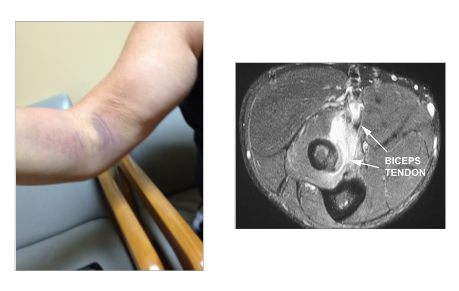

What is this?

Distal biceps tear